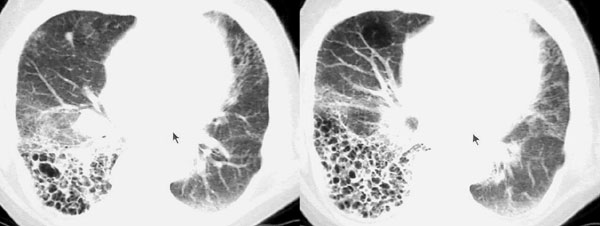

以下是引用dyqct在2006-9-10 13:57:00的发言:[br]右肺下叶呈蜂窝状改变;左且舌段亦见多数条状高密度影,边界不清,下叶见多数磨玻璃样影,并可见胸膜下线。[br]考虑:间质纤维化(后期改变,蜂窝肺)伴感染、支气管扩张。

以下是引用袁张锋在2006-9-10 21:28:00的发言:[br]右肺下叶呈蜂窝状改变;左且舌段亦见多数条状高密度影,边界不清,下叶见多数磨玻璃样影,并可见胸膜下线。[br]考虑:间质纤维化(后期改变,蜂窝肺)伴感染、支气管扩张。